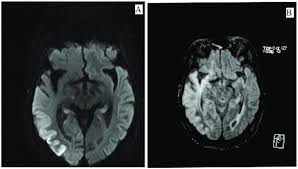

In children older than 3 months and in adults brain biopsy: Herpesviral encephalitis, or herpes simplex encephalitis (hse), is encephalitis due to herpes simplex virus. • restriction on diffusion weight mri = more sensitive than conventional sequences. Misra uk, hashmi aa, kalita j. Diagnostic uncertainty and empirical management in pcr negative encephalitis. It is a severe condition brain mri may show limbic encephalitis (55) or diffuse t2 and dwi hyperintensities in the white matter, associated with restricted diffusion (54). Herpes simplex encephalitis occurs as 2 distinct entities: Mri is the imaging of choice in suspected cases of viral encephalitis, although ct scanning may be used where mri facilities are not available. The patient had initially improved after medical treatment. Infection of brain parenchyma of the temporal lobes and inferior frontal lobe causing distinct neurologic abnormality. Dhawan a, kecskes z, jyoti r, kent al. Associated with hsv encephalitis (strong evidence). In addition, because of the involvement of the.

It is a severe condition brain mri may show limbic encephalitis (55) or diffuse t2 and dwi hyperintensities in the white matter, associated with restricted diffusion (54). Brain mri—increased t2 signal intensity in frontotemporal region → viral (hsv) encephalitis. Associated with hsv encephalitis (strong evidence). Provided cranial imaging has excluded any contraindications such as a space occupying lesion or severe cerebral oedema and brain shift, a csf. Having said that, mri with contrast is considered the most sensitive imaging modality, and findings are present in over half of individuals 8. In addition, because of the involvement of the. We performed volumetric measurements of the left and right temporal lobes and of cerebral oedema. Herpes simplex encephalitis occurs as 2 distinct entities: The study analysed serially acquired magnetic resonance images (mri), of patients with acute hsv encephalitis who had neuroimaging repeated within four weeks of the first scan. Pregnancy the most common cause of encephalitis in newborns is vaginal delivery from a mother who is infected with herpes simplex virus 2 (hsv 2). There is no particular age, sex, or seasonal predilection. Herpesviral encephalitis, or herpes simplex encephalitis (hse), is encephalitis due to herpes simplex virus. Severe infection, particularly untreated herpes simplex virus (hsv) encephalitis, can cause brain hemorrhagic necrosis.

• occurs despite blood brain barrier with tight junctions. Encephalitis in the immunocompromised host. Mri is the imaging of choice in suspected cases of viral encephalitis, although ct scanning may be used where mri facilities are not available. It is a severe condition brain mri may show limbic encephalitis (55) or diffuse t2 and dwi hyperintensities in the white matter, associated with restricted diffusion (54). Diagnostic uncertainty and empirical management in pcr negative encephalitis.